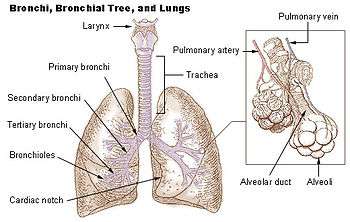

Bronchial anatomy

Bronchial anatomy Bronchi, bronchial tree, and lungs